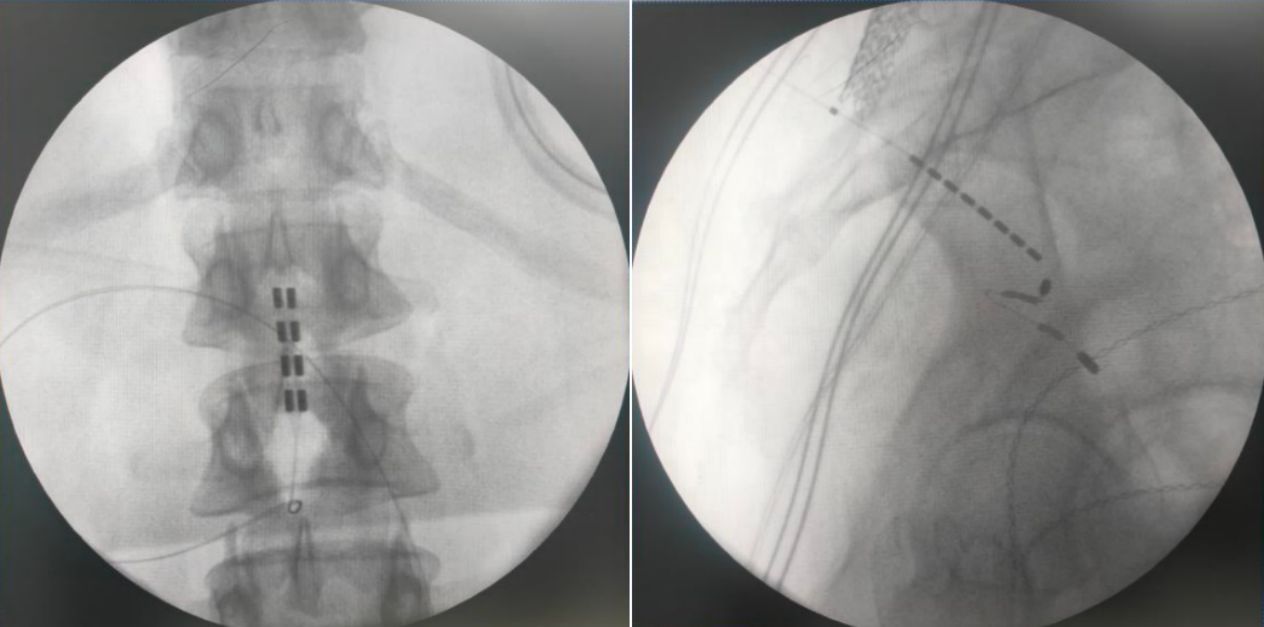

由于該患者為脊髓拴系,脊髓位置偏低,而且脊柱裂合并骶椎骨性解剖畸形給骶孔穿刺帶來了非常大的難度,但是通過術(shù)前的系統(tǒng)評估以及術(shù)中電生理監(jiān)測,李萃萃主任團(tuán)隊(duì)將一根穿刺電極精準(zhǔn)置入S3骶孔位置以改善二便功能,另一根4-4排布的片狀電極覆蓋L1-2節(jié)段(患者脊髓低位,放置位置需根據(jù)患者情況個(gè)性化調(diào)整)以調(diào)控下肢肌張力異常和感覺障礙。術(shù)中測試顯示,骶神經(jīng)刺激可有效引發(fā)二便感知,脊髓電刺激則完整覆蓋臀部及雙下肢。